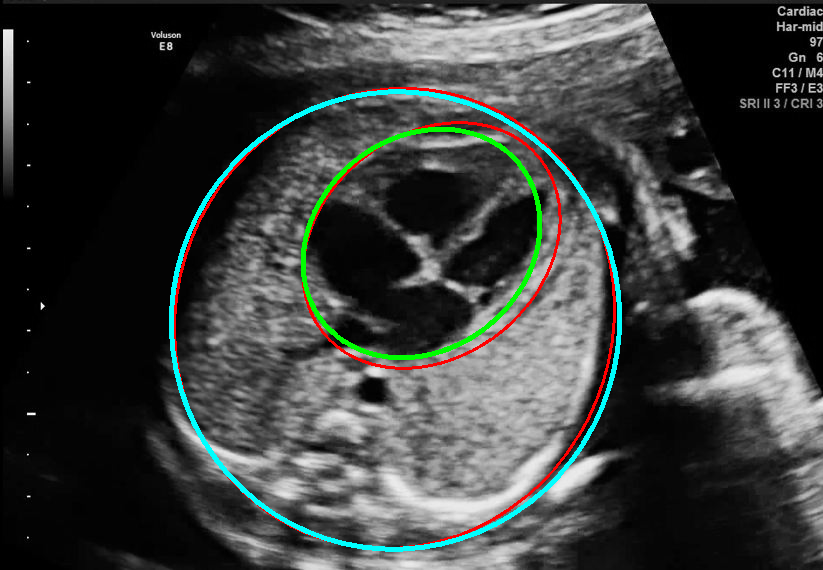

Visualization results of different methods.

Although the segmentation model trained on the fetal ultrasound dataset achieves a relative high average dice scores averaging over 0.9, the fitted ellipse highly depends on the segmentation results. As shown in the middle row of Fig. 2, the segment-based ellipse-fit method performs well when the image quality is good (first row), but the performance degrades when the segmentation is affected by image artifacts such as the acoustic shadowing (second and third row). Our proposed method is more robust to image quality and shadows. We also tried to compare to the GPN [9] with their open source code on our dataset, however, the results are not comparable to ours and those presented in Table. 1. It is difficult to conclude whether it is caused by the network itself or the training strategies. We, therefore, did not include the comparative results in this work.

As shown in Fig. 3 , both the proposed ellipse regression loss and IoU loss are necessary for ellipse detection. If the EllipseNet only supervised by IoU loss (first column), the model fails to optimize the major and minor axis separately, and the predicted ellipses degenerate into circles like the CircleNet. It is clear that the supervision of IoU loss can help to improve the prediction of location and shape (first and second row) and to correct the angle (last row).